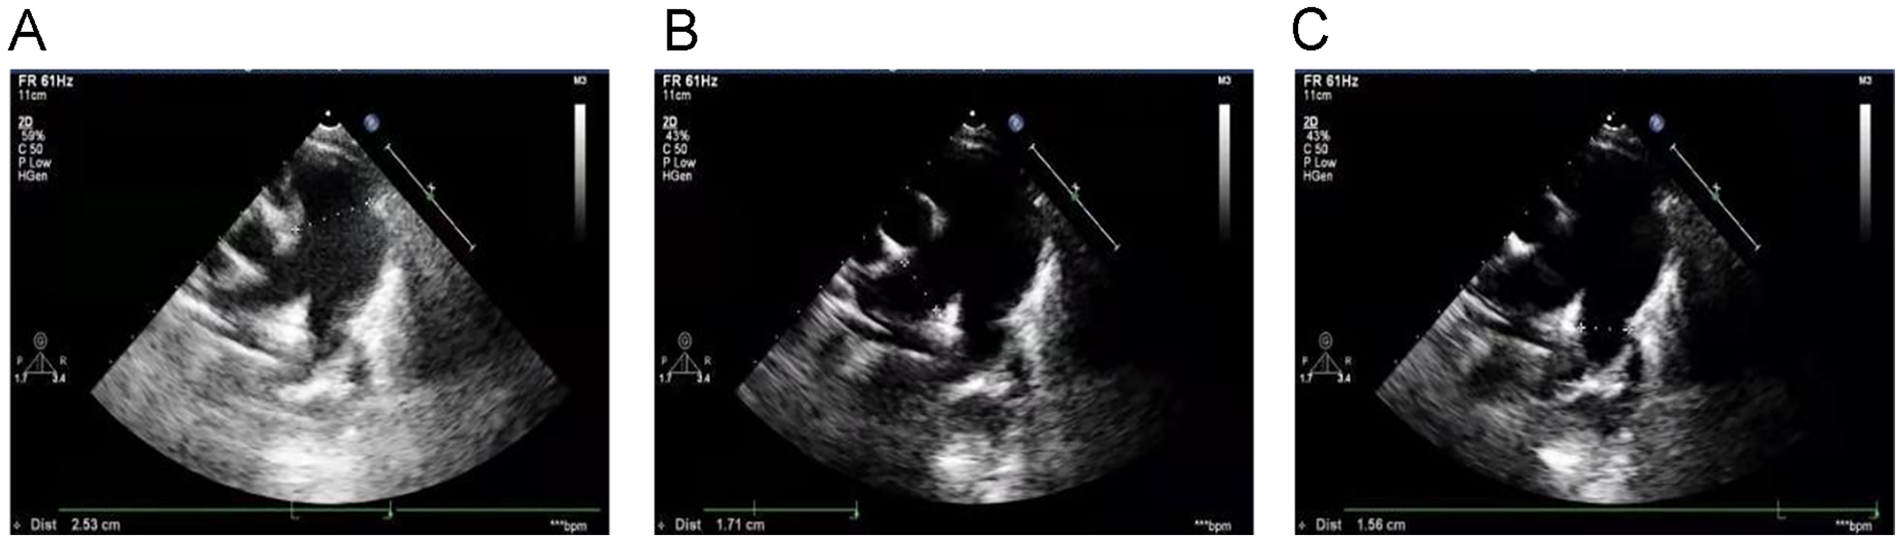

Echocardiography with tissue Doppler imaging (TDI) and ejection fraction (EF) measurement was subsequently performed and showed main pulmonary artery and branch dilation: main pulmonary artery diameter: 25 mm (Z-score: 5.32) (Figure 2A), right pulmonary artery diameter: 17 mm (Z-score: 6.08) (Figure 2B), left pulmonary artery diameter: 16 mm (Z-score: 5.3) (Figure 2C). The systolic pulmonary artery flow velocity was 1.1 m/s. During diastole, a small amount of regurgitation was observed, with a peak regurgitation velocity of 2.36 m/s and a pressure gradient of 22 mmHg.

Figure 2

Echocardiography with TDI and EF measurement: (A) main pulmonary artery diameter (25 mm), (B) right pulmonary artery diameter (17 mm), (C) left pulmonary artery diameter (16 mm).